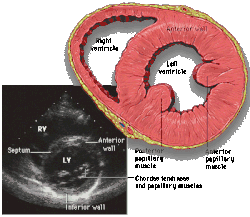

|  Subcostal four chamber |  Apical four chamber |  Parasternal long axis  |  Parasternal short axis  | ||||||||

| Each figure contains a TTE with a black background, and a corresponding colored illustration. | Patrick J. Lynch and C. Carl Jaffe, Yale University, 2006. | ||||||||||

| Click on a figure to enlarge it and see some parts of the heart identified. RV, right ventricle; LV, left ventricle; RA, right atrium; LA, left atrium; TV, tricuspid valve; MV, mitral valve; AV, aortic valve; RVOT, right ventricular outflow tract; LVOT, left ventricular outflow tract | |||||||||||